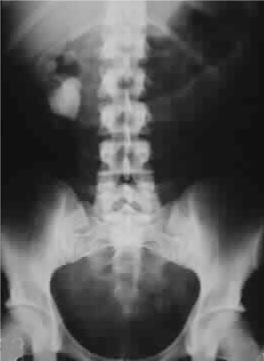

DXA scan of Spine with severe osteoporosis

Bone disease (low bone density and osteoporosis) is common but less frequently associated with fractures than in the past. As bone disease may only present clinically and radiologically at an advanced stage, bone densitometry of cortical bone is required to demonstrate osteoporosis in patients with general aches in the context of pHPT.